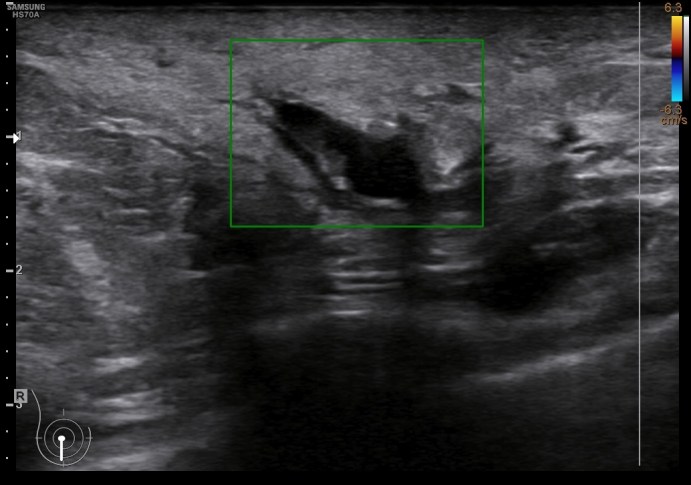

En la imagen 3 puedes ver un absceso, complicación de una mastitis, cuyo aspecto es el de una colección anecoica, que si observas, quieres buscar la superficie de la piel. La imagen 4 y 5 es el estudio de la lesión en trasnverso u otro plano y el estudio doppler buscando posible vascularización a ese nivel.